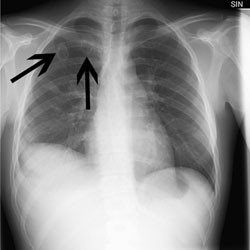

Røntgen thorax to uker senere viste tilbakegang av lungefortetningene. Ultralydundersøkelse av halskar med tanke på tromboflebitt var negativ. Hun var subfebril på kveldstid. Blodprøver viste SR 108 mm/t og CRP 9 mg/l. Hun opplyste nå at hun under hele sykdomsforløpet hadde hatt vedvarende smerter i høyre hofte og lår. MR av høyre hofte tre uker etter utskrivning viste koksitt, men man avsto fra leddpunksjon for å forhindre iatrogene komplikasjoner (fig 2). Man fortsatte med konservativ behandling med metronidazol.

CT thorax fire uker etter utskrivningen viste betydelig tilbakegang av lungefortetningene. MR av høyre hofte tatt samtidig viste litt økende signal i beinmargen i høyre caput femoris, det kunne være en begynnende osteomyelitt. SR var 40 mm/t og CRP < 5 mg/l.

Pasienten var symptomfri først seks uker etter utskrivningen. Man forsatte metronidazolbehandlingen i ytterligere fire uker. Pasienten fikk dermed antibiotika i til sammen tre måneder. MR høyre av hofte ni uker etter utskrivning viste tilbakegang av koksitt og ingen tegn til osteomyelitt. Ved kontroll seks måneder etter sykdomsdebut var pasienten symptomfri, hadde CRP < 5 mg/l og normalt røntgen thorax.